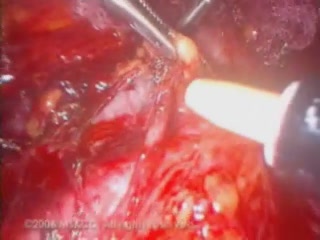

Partial Bladder and Ureter R..

Partial Bladder and Ureter R..

Farr R. Nezhat, MD, FACS / CINE-MED